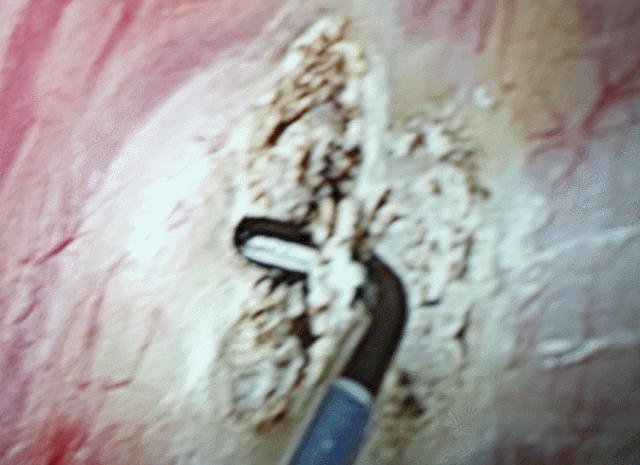

郭建极介绍,通过胸腔镜手术,只需要在腋下胸壁做一个0.5cm的隐蔽小切口置入胸腔镜,然后用特制的器械切断支配手部汗腺的交感神经,通常不到半个小时就可以解决问题。

更为重要的是,该术式创伤小,恢复快的特点。术中,几乎无出血,术后也不需要放置胸腔引流管。